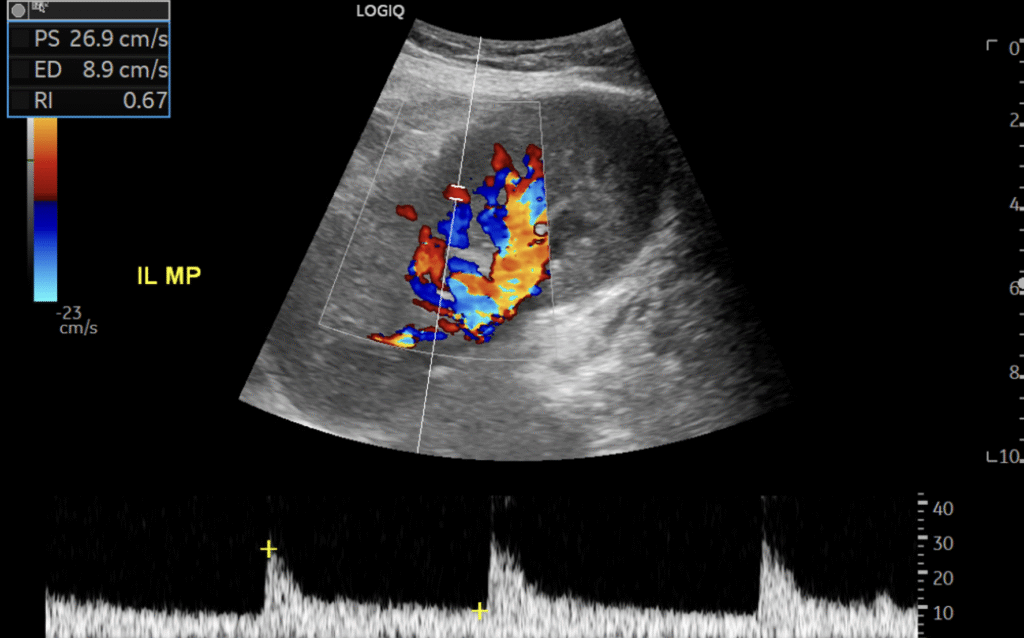

Am J Transplant. 2025 Sep 10:S1600-6135(25)02949-1. Bodard S, Pierce TT, Sertic M, Lafargue MC, Samir AE, Riella LV. Abstract: Early and accurate detection of posttransplant complications is critical for preserving…